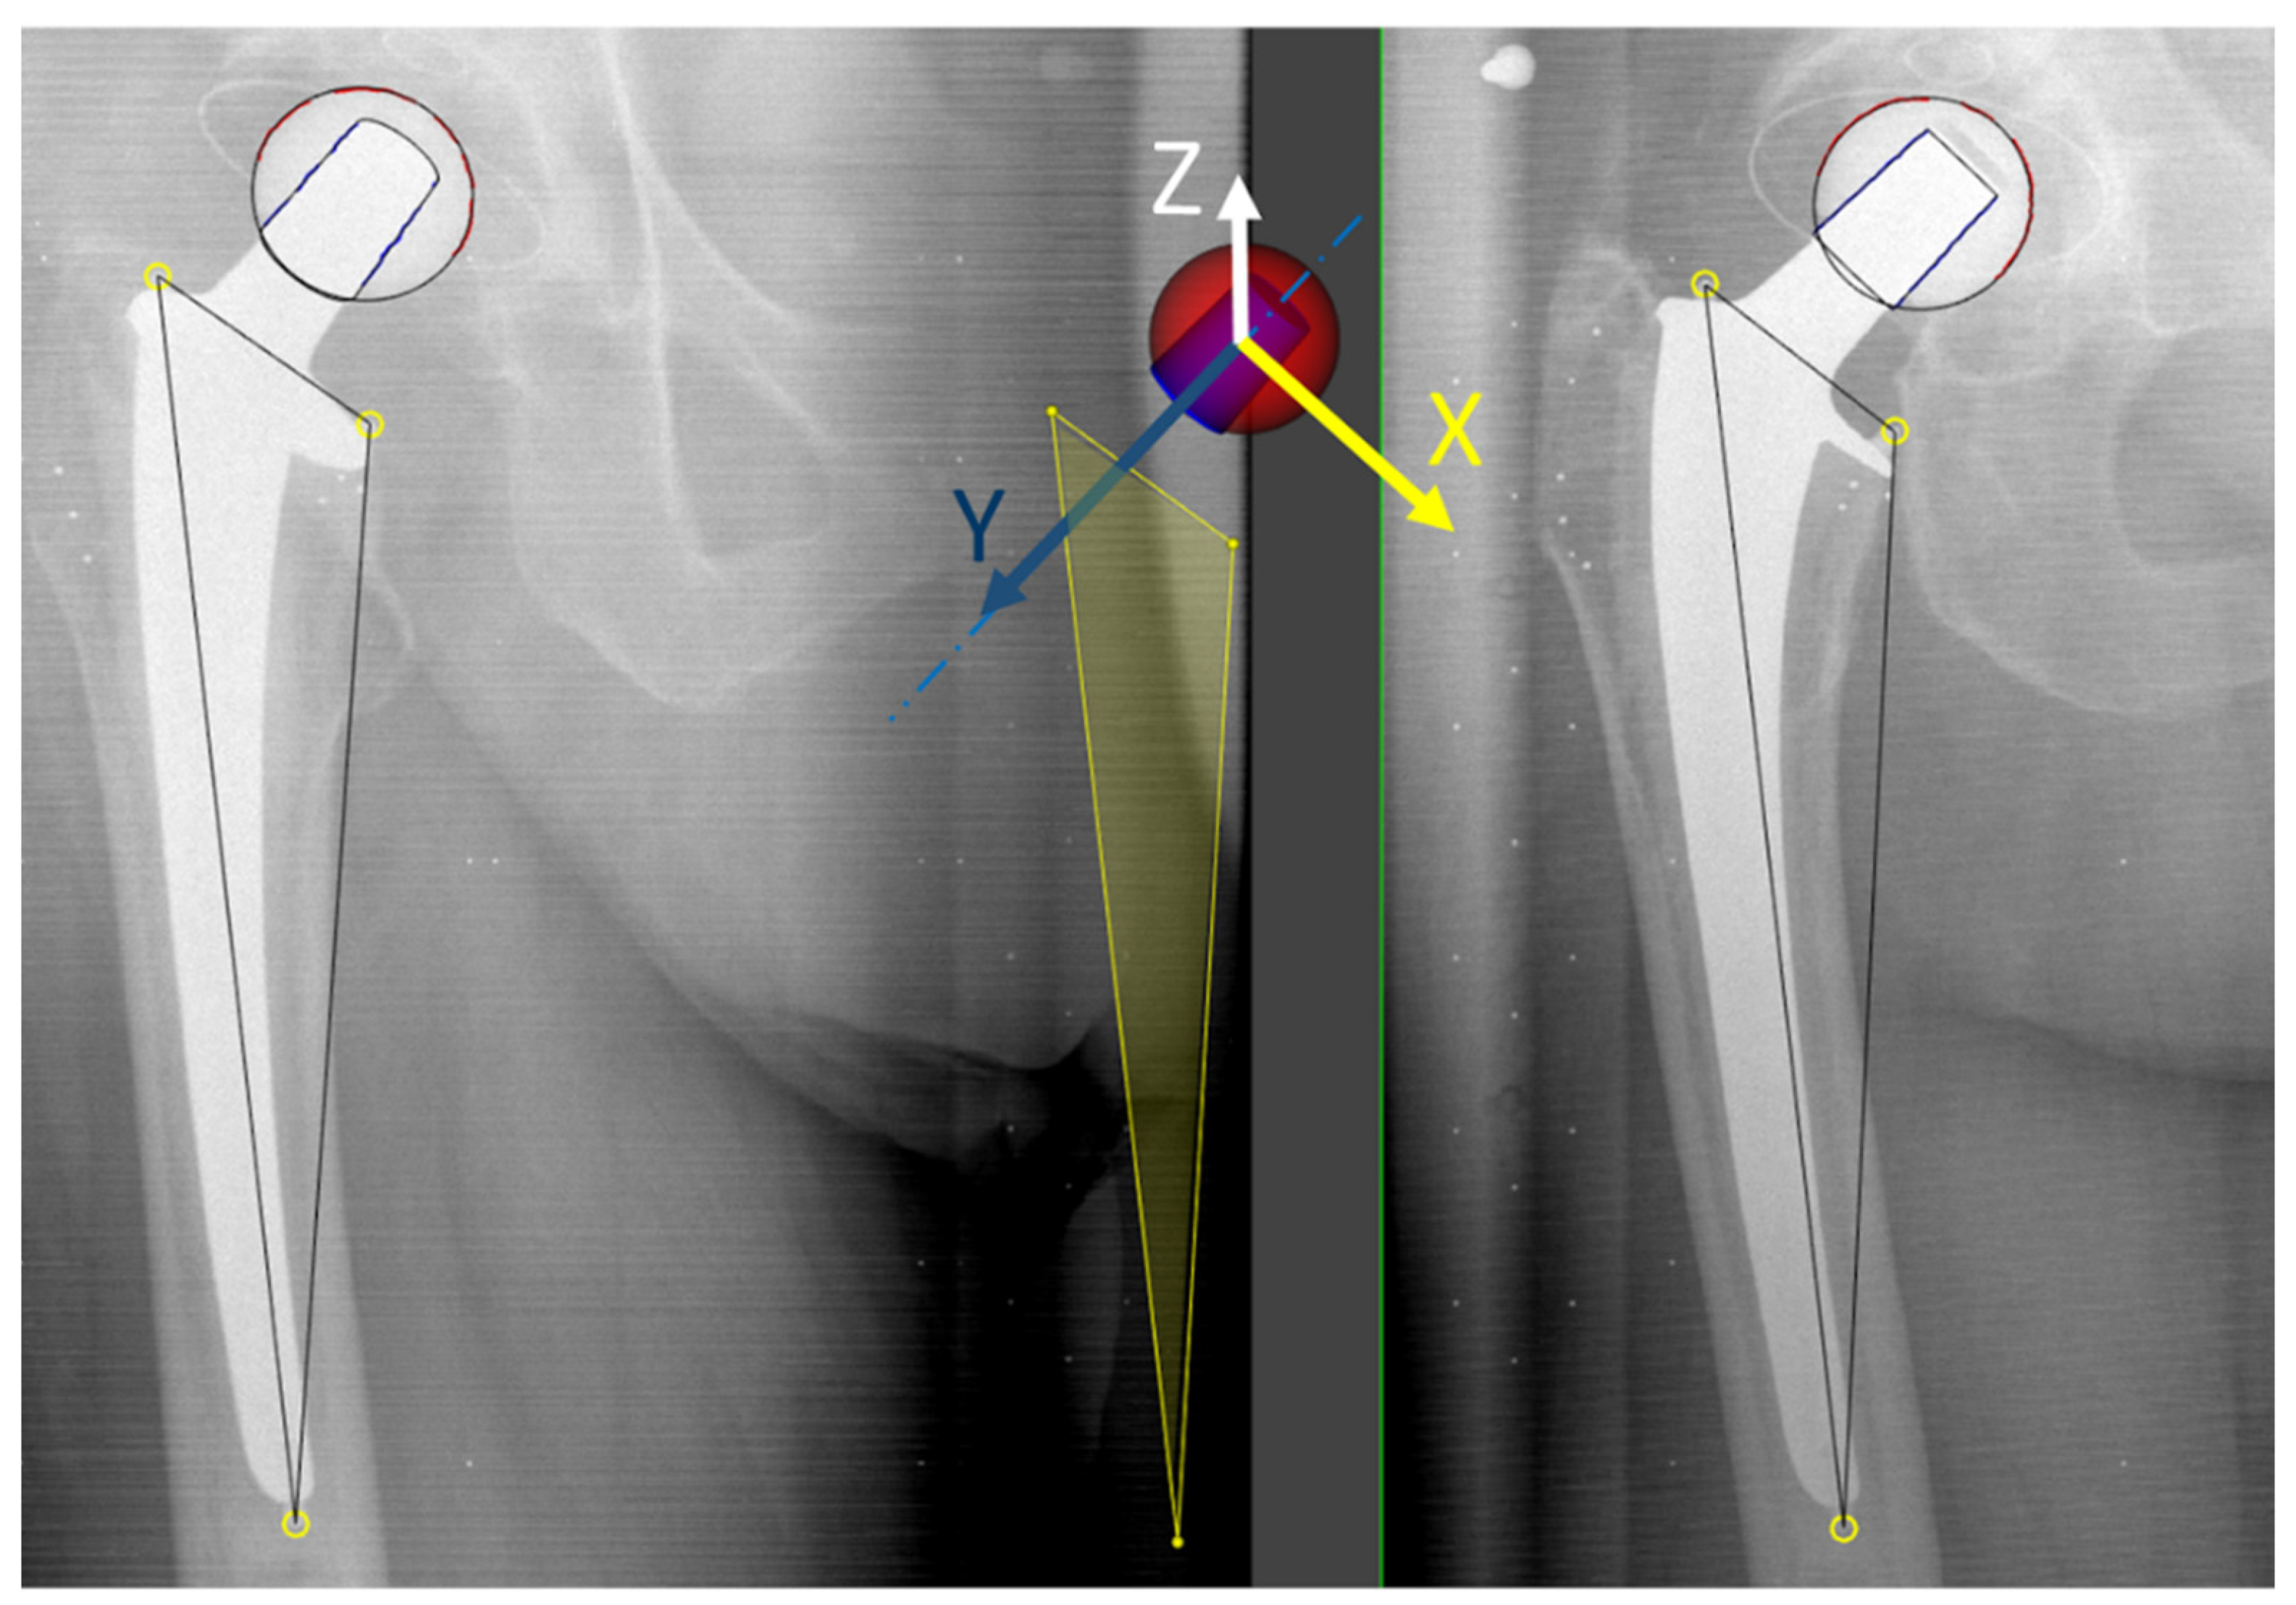

2.2. Image Acqusition and Analysis

2.3. Head–Taper Migration Measurements